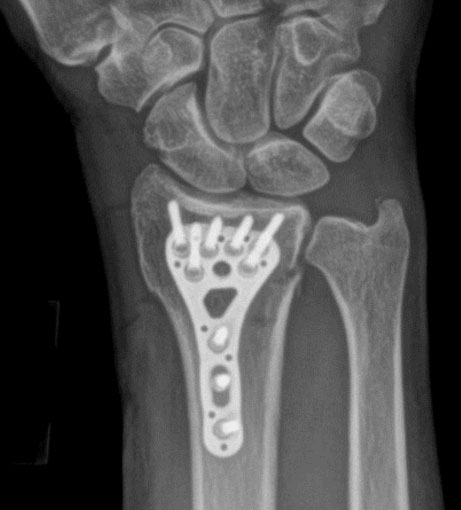

Distal Radius Plating System

Our Distal Radius Plates, provide variable angulation while providing a locked rigid construct. Made from titanium, they are low profile with simple instrumentation reducing the clutter on the operating room back table.

System Features

• Anatomic Plate Contour

• Low profile locking plate technology

• Titanium construction

• Locking and non-locking screws

• 15° Variable-angle locking technology

• Multiple options for distal screw fixation

• Multiple plate widths and lengths

xray1